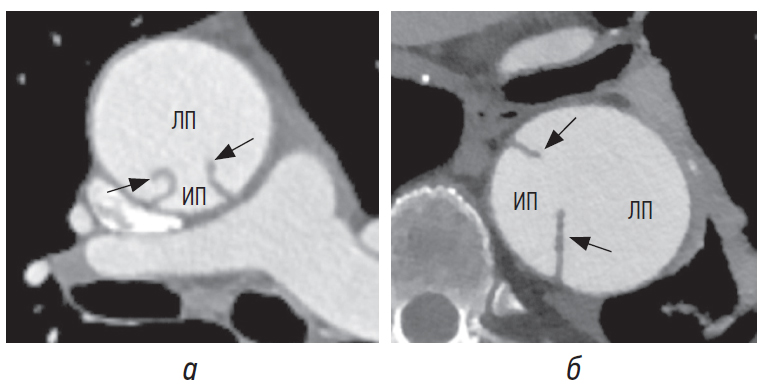

Для острой диссекции более характерны заметная кривизна и волнистость подвижного лоскута (рис. 7, а), тогда как для хронической диссекции — плоский, фиксированный и утолщенный лоскут на большем его протяжении (рис. 7, б) [6–8].

Рис. 7. Интимомедиальный лоскут (стрелки) при острой (а) и хронической (б) диссекции. ИП — истинный просвет, ЛП — ложный просвет

Направление кривизны лоскута в сочетании с другими признаками помогает отличить истинный просвет от ложного, поскольку лоскут чаще всего изогнут в сторону ложного просвета (рис. 8, а) и реже — в сторону истинного (рис. 8, б) [8].

Рис. 8. Интимомедиальный лоскут кривизной (стрелки) обращен в сторону ложного просвета (а), в сторону истинного просвета (б). ИП — истинный просвет, ЛП — ложный просвет

Потеря кривизны, волнистости и подвижности лоскута обусловлены тем, что со временем лоскут фиброзируется с образованием неоинтимы, приводя к утолщению и ригидности лоскута. Это объясняется также тем, что по мере расширения ложного просвета линии, по которым диссекционный лоскут соединяется с внешней стенкой аорты, раздвигаются, туго натягивая лоскут [6–8, 10].

Свободные края интимомедиального лоскута значительно чаще наблюдаются при хронической диссекции по сравнению с острой, что может быть обусловлено утолщением, укорочением и снижением подвижности лоскута.

В некоторых литературных источниках приводится интересный факт — свободные края интимомедиального лоскута направлены в сторону ложного просвета (рис. 9, а, б) [7, 9]. Авторы, учитывая динамический характер интимомедиального лоскута, предполагают, что свободные края разрыва могут указывать и на истинный просвет [9].

Рис. 9. Свободные края интимомедиального лоскута (стрелки) направлены в сторону ложного просвета в восходящем отделе (а), в нисходящем отделе (б). ИП — истинный просвет, ЛП — ложный просвет